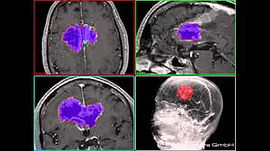

2.Segmentation:- Segmentation in Image Processing is being used in the medical industry for efficient and faster diagnosis, detecting diseases by identifying specific pixels in an image that contains a structure or finding.

Use case- Identify tumors and calculate the size of the abnormality.

Source: Chimaera GmbH gallery